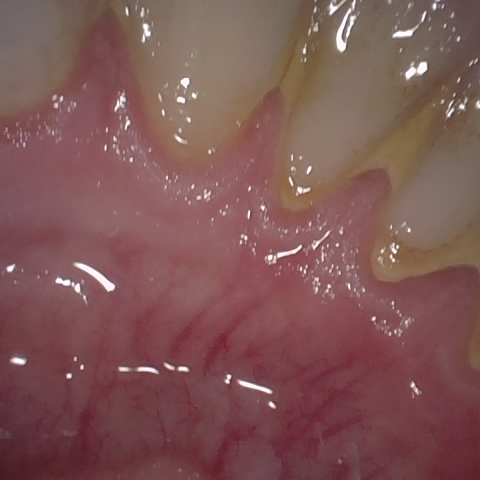

Annotated as "Bad"